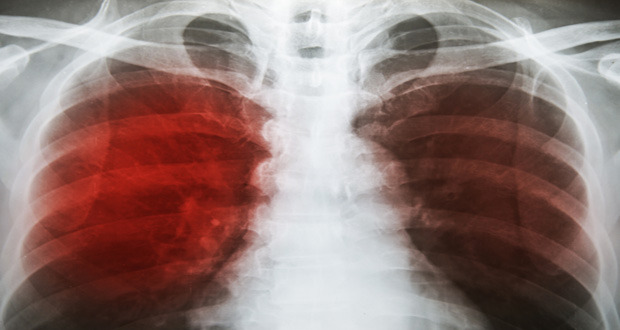

After all, Tuberculosis (TB) is more commonly found at the tragic ending of an opera than in the news headlines. This is despite the fact that the World Health Organisation (WHO) estimate that in 2016, 10.4 million people fell ill with TB, and 1.7 million died from the disease. In fact, TB is one of the top 10 causes of death worldwide.

Mycobacterium Tuberculosis (Mtb) – the bacteria that causes tuberculosis – survives and replicates within the host’s cells. The bacteria’s primary targets are alveolar macrophages, immune cells essential for the human body’s natural defence against disease. However, Mtb thrives in this hostile environment. One way Mtb alters the cellular environment around it is to secrete various substances. These virulence factors have been shown to manipulate cell activity and disrupt signalling, suppressing the innate immune response.